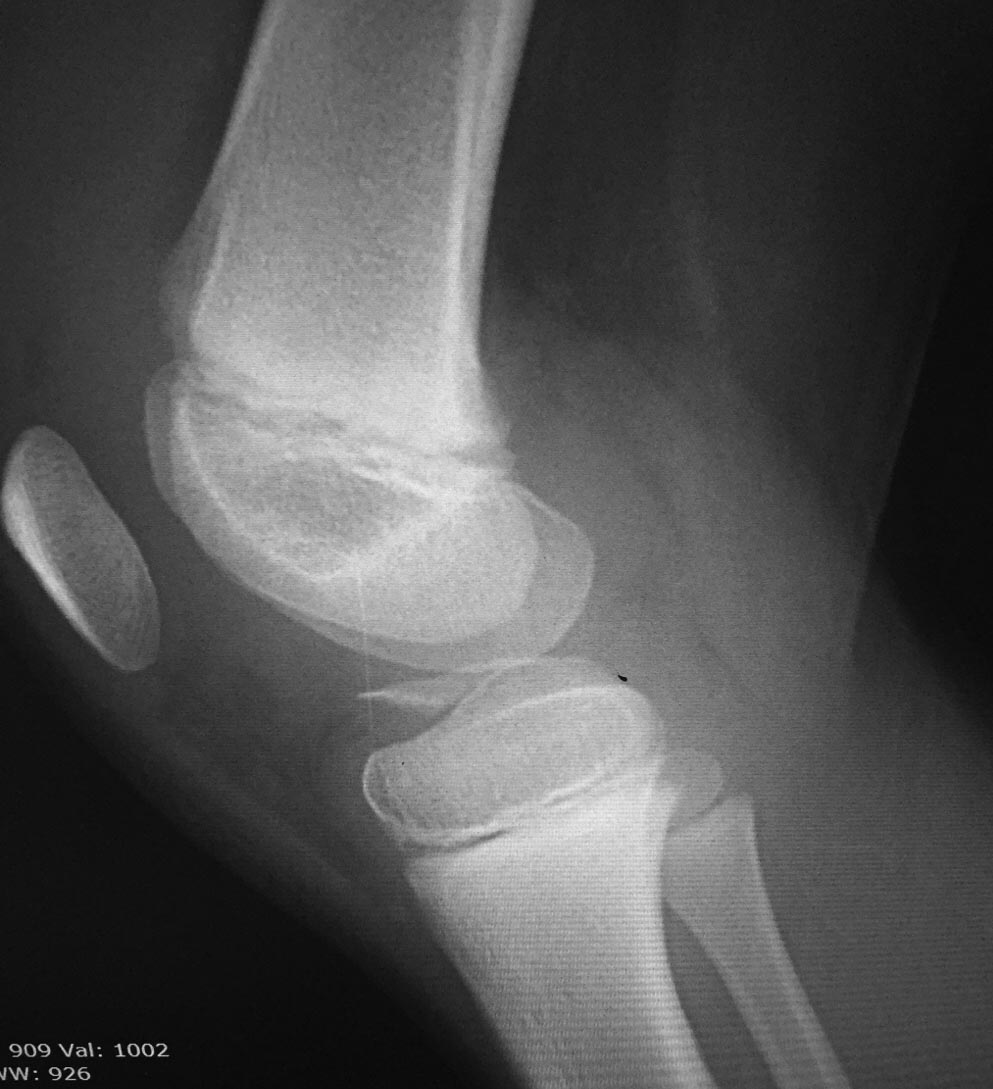

Перелом сегонда.

Пациент 8 лет, девочка. Перелом межмыщелкового возвышения по 2 типу. Есть артроскоп, но все что мы можем сделать это диагностика, к сожалению. Кто имеет опыт подскажите как лучше поступить. Заранее благодарю.